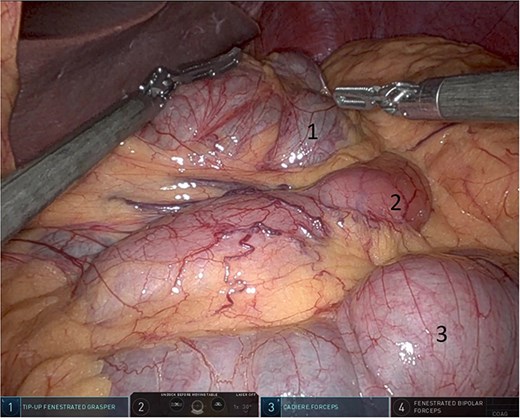

Upon entering the abdominal cavity, dilated bowel loops were observed (Fig. 2), and a significant portion of the colon was found herniated through the foramen of Winslow (Fig. 3). The herniated colon was covered by the pars flaccida (Fig. 4) (Video S1). Careful dissection was performed anterior to the hepatoduodenal ligament (Fig. 5). The gall bladder was retracted to the patient's right upper quadrant, which allowed for the retraction of the foramen of Winslow (Fig. 6) (Video S1). After carefully placing the tip of the instrument posterior to the portal vein and gently elevating it, the herniated colon was successfully reduced (Fig. 7) (Video S1).

Gallbladder was retracted to the patient's right upper quadrant which allowed for the retraction of the foramen of Winslow and anterior mobilization of it (1: gall bladder, 2: herniating colon, 3: first part of the duodenum, 4: portal vein).